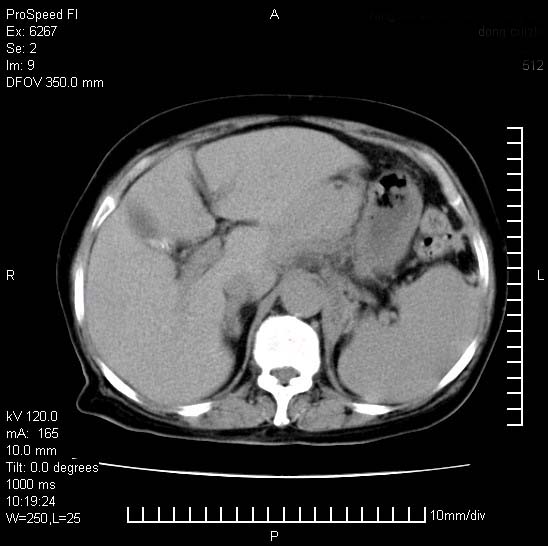

患者糖尿病,腹痛,恶心,呕吐。黄疸,意识较差,血糖很低(数值不详),临床以胆囊,胆管炎,低血糖反应收治。看的腹片少,各位帮忙看看,胰腺有问题吗??

胆囊炎,胆石症;胰腺炎可以确定,但需要增强,除外肿瘤

1.胰腺体积增大,胰周脂肪间隙消失,胰腺炎可以确定。必要时实验室进一步检查。

2.胆囊炎,胆石症。

胰腺体积增大,胰周脂肪间隙消失,考虑胰腺炎。胆囊炎,胆石症。

脾大,原因?胆结石;胰腺肿大,边缘模糊,建议查定性指标血尿淀粉酶,除外胰腺炎